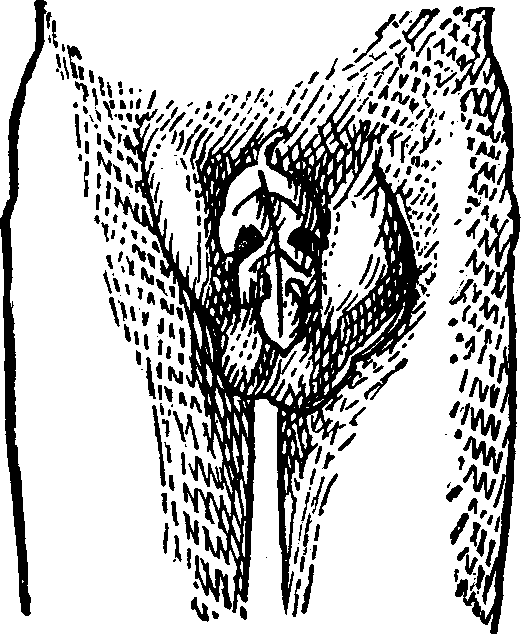

Fig. 3. THE UTERINE DILATOR. This instrument is introduced

into the canal of the uterine neck with its blades closed. By means of the

thumb-screw the blades are then separated as shown in this illustration,

the cervical canal being thereby dilated to the required extent.

Treatment. From the nature of this malady, it will readily be seen that no medical treatment can effect a radical cure. We must therefore resort to surgery. In a small proportion of cases, the stricture may be cured by repeated dilations of the constricted part of the cervical canal. This may be accomplished by using a very smooth probe which is fine at the point, but increases in size, so that its introduction will widen and expand the orifice and canal. The stricture may be overcome in many cases by using different sized probes. In some instances, we have employed the uterine dilator, represented by Fig. 3. We have also introduced sea-tangle and sponge tents into the neck of the womb, and allowed them to remain until they expanded by absorbing moisture from the surrounding tissues. The latter process is simple, and in many cases preferable. By means of a speculum (see Figs. 15 and 16), the mouth of the womb is brought into view, and the surgeon seizes a small tent with a pair of forceps and gently presses it into the neck of the womb, where it is left to expand and thus dilate the passage. If there seems to be a persistent disposition of the circular fibers of the cervix to contract, and thus close the canal, a surgical operation will be necessary to insure permanent relief. In performing this operation, we use a cutting instrument called the hysterotome (see Figs. 4 and 5). By the use of this instrument, the cervical canal is enlarged by an incision on either side. The operation is but slightly painful, and, in the hands of a competent surgeon, is perfectly safe. We have operated in a very large number of cases and have never known any alarming or dangerous symptoms to result. After the incision, a small roll of cotton, thoroughly saturated with glycerine, is applied to the incised parts, and a larger roll is introduced into the vagina. The second day after the operation, the cotton is removed, the edges of the wound separated by a uterine sound or probe, and a cotton tent introduced into the cervix, and allowed to remain, so that it will expand and thus open the wound to its full extent. This treatment must be thoroughly applied, and repeated every alternate day, until the incised parts are perfectly healed.